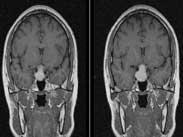

• 垂體卒中